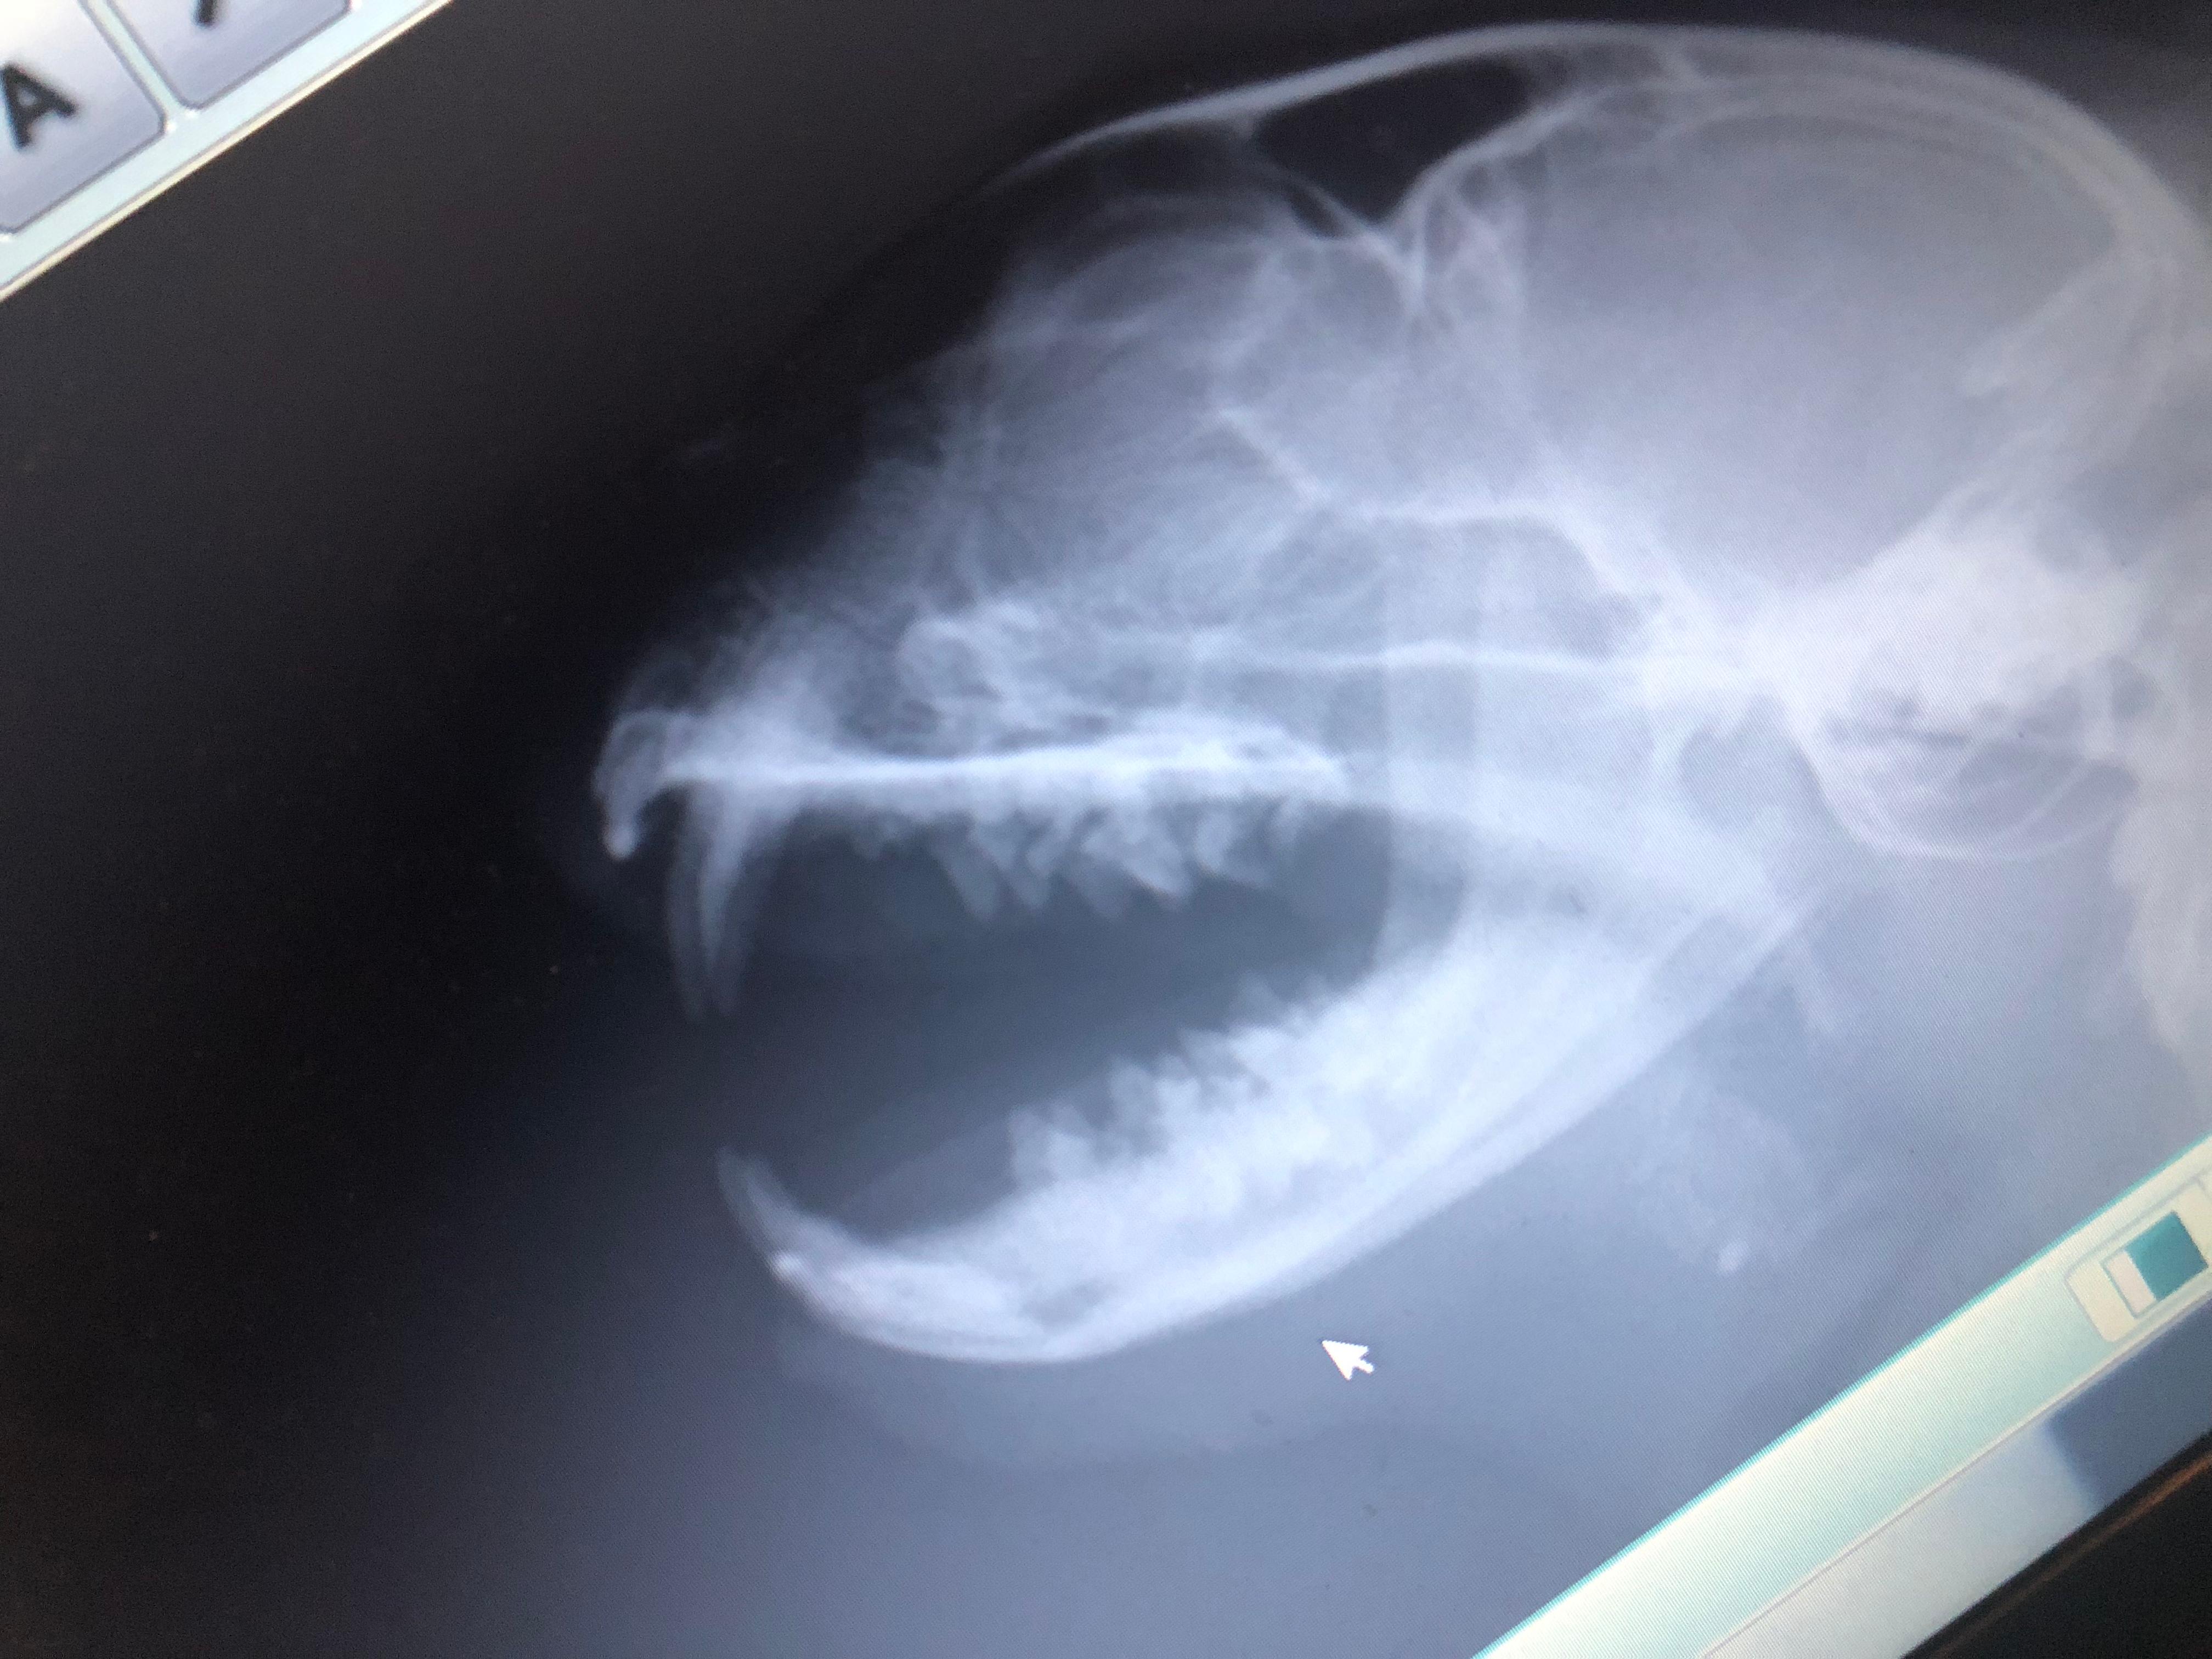

Hi. My cat have a breathing problem. In the photos you can see an object in noise. But no one couldnt undertand And ı have A video . You can hear the Voices.

This could be a polyp or a tumor or a foreign object. This will need to be removed. If your local vet cannot remove that, you may need to take your cat to a clinic in a larger city or at the veterinary hospital at the nearest veterinary university. Unfortunately without seeing the cat's nose with the foreign body, there is no way I can suggest a treatment or possible cause.